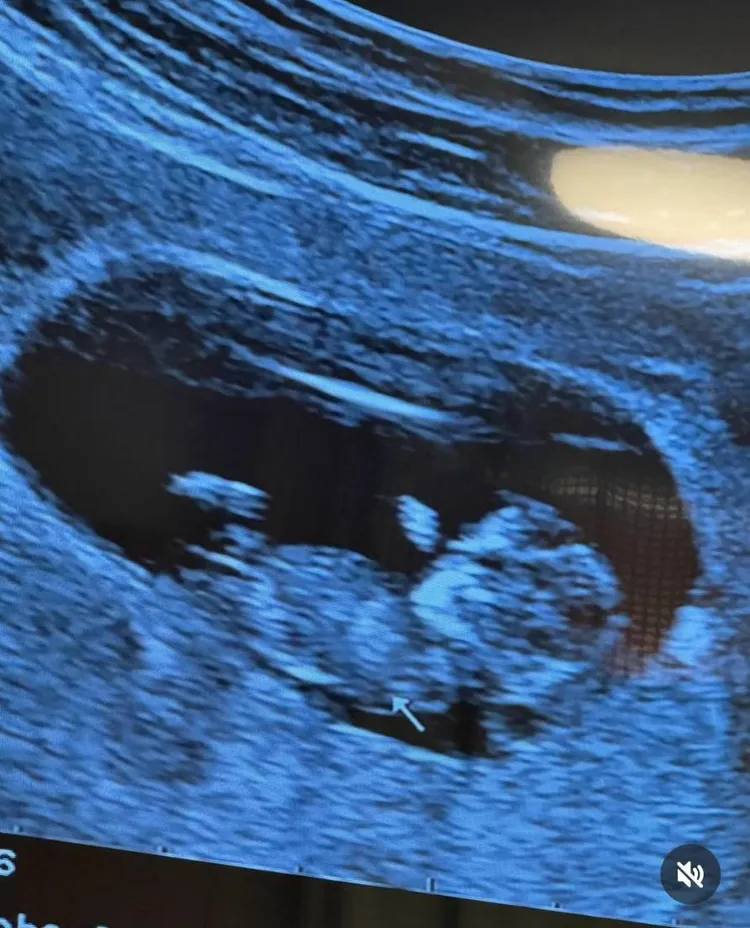

對此,洪小鈴的經紀人證實兩人已在先前登記結婚,並且懷孕,現在較為穩定,所以和大家分享喜訊,被問登記結婚有挑特別日子?她經紀人說:「沒有特別,他們兩人很隨性就翻個農民曆,然後問我那天有沒有空當他們證人,就去了這樣。」一路見證兩人愛情的經紀人非常祝福他們。